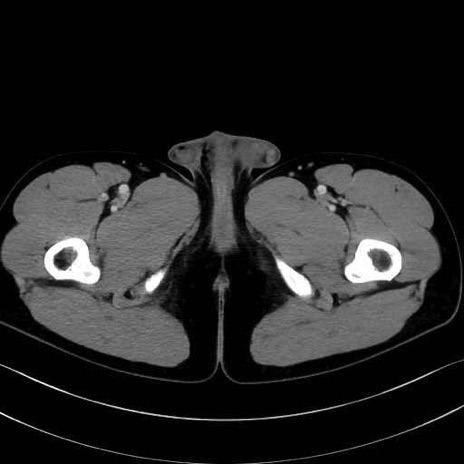

小殿筋 (Gluteus minimus)